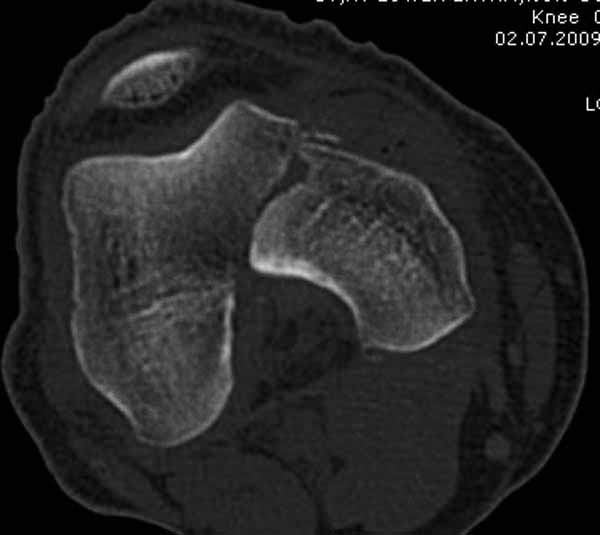

Представленный снимок не дает полную информацию. Там вроде простой перелом, но на самом деле, кроме смещенного (латерального, возможно медиального?) мыщелка на второй проекции имеется медиальный короткий дистальный фрагмент в флексии. Надо было сделать прямой снимок с захватом малоберцовой, который ориентировал бы стороны. Без КТ обычный снимок в дистракции поможет разобраться в топографии фрагментов.

Кстати, из вашего снимка, если отмечены вашим рентгенологом правильно, тогда получается снимок левого колена, и, соответственно, длинный переходящий в диафиз мыщелковый фрагмент находится медиально. Если так, тогда меняется сценарий фиксации!!!

И не обратите, коллега, пока не сделаете четкие анфасные снимки (лучше с дистракцией) где будет четко визуализироваться малоберцовая кость. Думается, что и КТ здесь будет уместно, дабы не пропустить возможное флексионное повреждение (перелом Hoffa).

А теперь по поводу лечения перелома. Среди всех чрез/меж-мыщелковых переломов в 38% сопровождются переломом в корональной плоскости, т.е перелом Hoffa. Nork et al, J Orthop Trauma, 87:564, 2005.

У больных как в этом случае, с вовлечением двух мыщелков правильно, что сделали вытяжение до операции. Здесь имеется флексионный компонент на другой стороне, и я бы рекомендовал операцию делать из двух доступов. Сперва фиксировать медиальную колонну custom made пластиной, обычно 1/3 тубулярной пластиной в 4.5 мм, потому что пока производители опаздывают с медиальной пластиной.

Здесь пример медиальной пластины и латеральный комбинированный метод (у второго больного старый перелом тибиал плато, леченный где то и когда то)